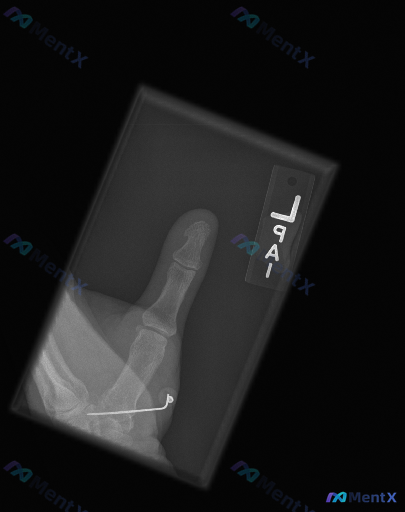

整理到一张左侧拇指的术后X光片,先放一下基础影像信息: - 部位:左侧拇指(正位) - 背景:有近期骨科手术史 - 常规报告印象:第一掌骨基底部可见内固定(克氏针)在位,未见新发骨折征象或内固定失效表现 不过这份深度分析报告里提了几个不一样的视角,甚至说「不是单纯的正常术后复查」。 想先问问大家:只...